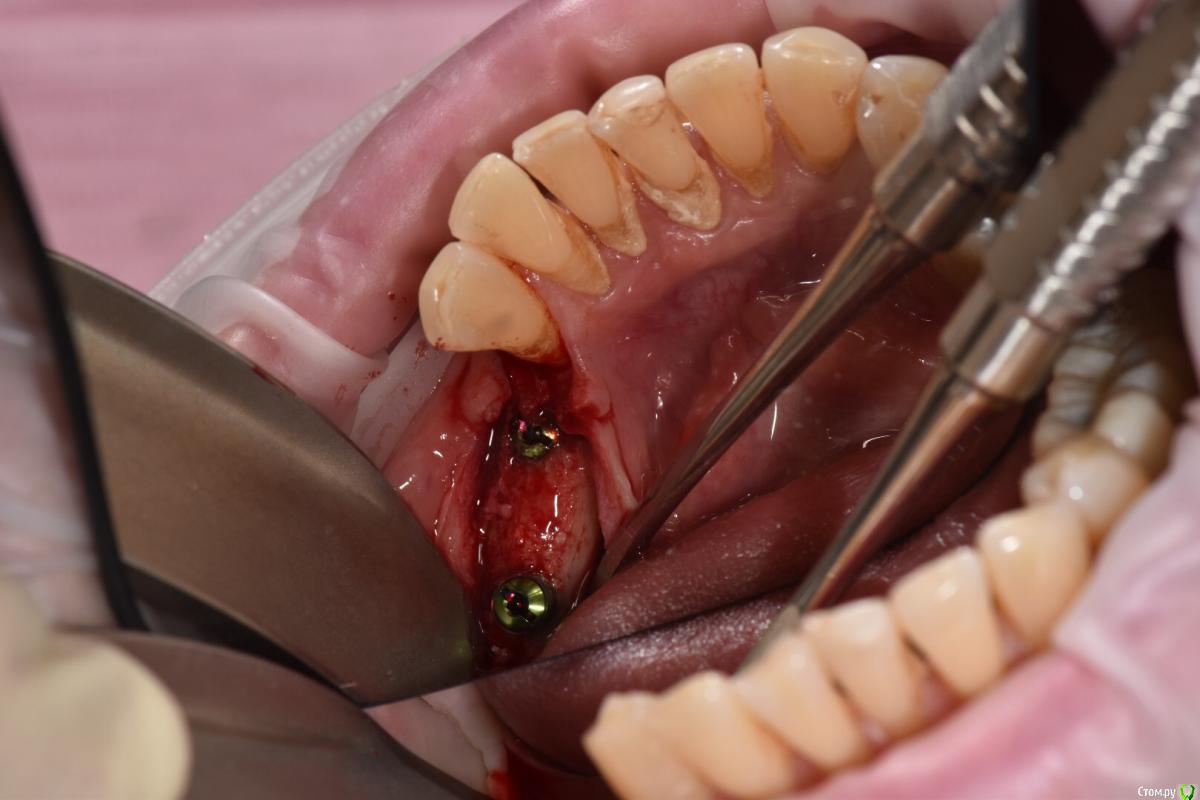

Santi Опубликовано 18 сентября, 2018 Поделиться Опубликовано 18 сентября, 2018 Имеем Концевые деффекты н/ч. Справа по плану НКР+импланты в позициях 4-6, слева импланты+ десна Итог сразу после Через 5-6 месяцев имеем такую картину Сразу после мягкотканной пластики И через пару месяцев Заранее пардоньте за качество фото и отсутствие картины ДО Ваше мнение коллеги ? 3 Ссылка на комментарий

Santi Опубликовано 19 сентября, 2018 Автор Поделиться Опубликовано 19 сентября, 2018 Этапов аугументации к сожалению нету. То , что выложил + этап раскрытия Ссылка на комментарий